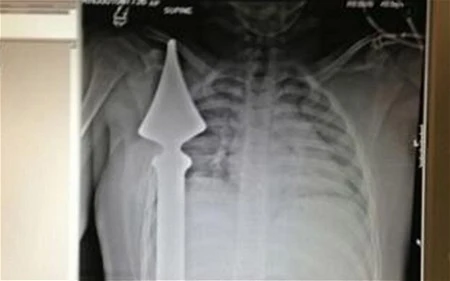

Hình chụp phim X-Quang cho thấy cọc nhọn hàng rào đâm xuyên qua người cậu bé

Các bác sĩ cho biết cậu bé Josh đã rất may mắn khi thanh sắt đã không chạm vào bộ phận quan trọng nào trong cơ thể như tim hay phổi. Đáng chú ý, thanh sắt này cắm xuyên qua người cậu bé chỉ cách tim 6cm. Nếu lệch qua một chút, hẳn cậu bé đã không thể được cứu sống.